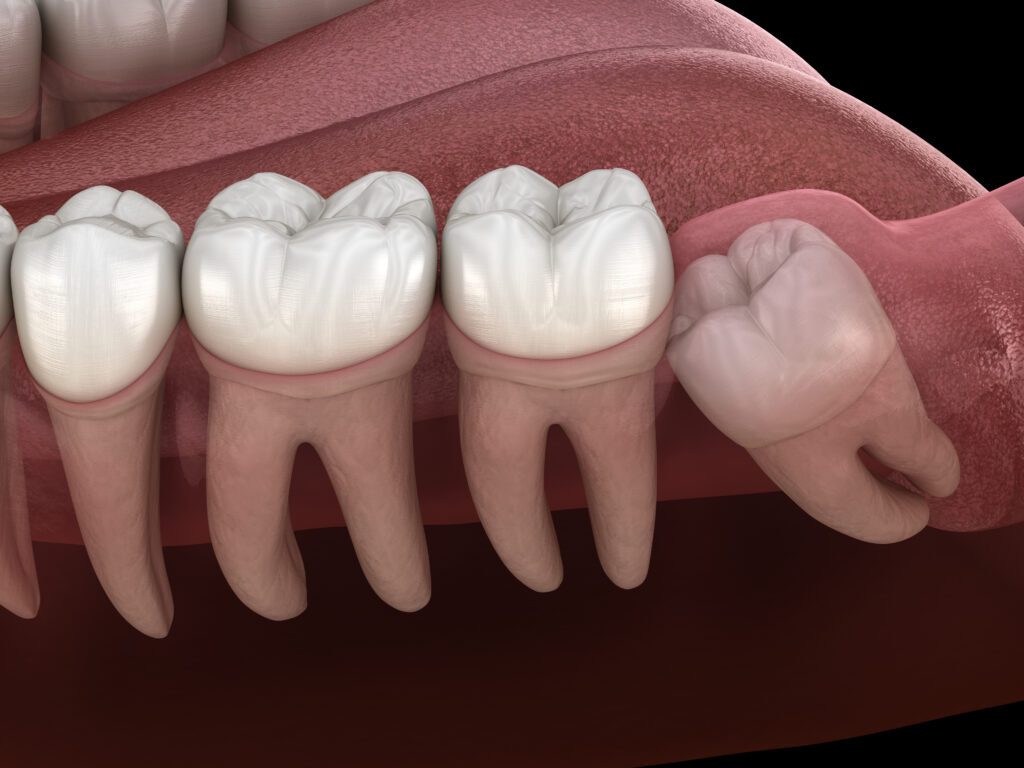

斜め・横向きに生えてきている場合

スペース不足で親知らずが横向きになっていると、手前の歯とのすき間に汚れがたまりやすく、虫歯や歯周病の原因になります。

特に親知らずだけでなく、健康な 隣の歯を傷めてしまう ことが大きな問題です。

隣の歯に当たっていて歯並びを押している

手前の歯(第二大臼歯)を押すことで

前歯がガタガタになるなど 歯並びへの影響 が出ることがあります。